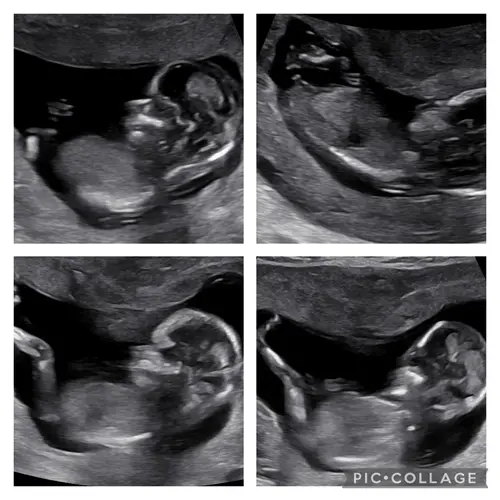

Iemand een idee? In de vorige topic 2x meisje 1x een jongentje werd er gezegd maar vandaag een nieuwe echo gehad bij de 13.4 weken vandaar nogmaals de vraag 😊

Reactie op Wensmoeder0546

Iemand een idee? In de vorige topic 2x meisje 1x een jongentje werd er geze ...

Geen nub te zien

Kan je toevallig hierin wel wat zien haha?